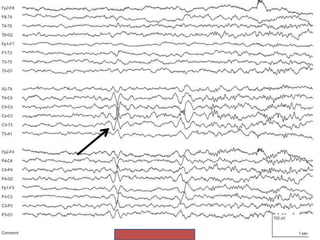

Subclinical Rhythmic Electrographic

Discharge of Adults (SREDA)

• Abrupt onset and termination of sharp rhythmic theta rhythm of

5-7Hz

• Constant frequency

• Duration of 40-80 sec

• Located Parietal and Posterior temporal

• Bilateral and synchronous, symmetrical (however sometimes

unilateral)

• No change in localization of frequency

• Present in wakefulness, drowsiness, stage II sleep

• Trigger: Hyperventilation

• Usually in people >50 years

• Uncommon (incidence <0.05%)

Subclinical Rhythmic Electrographic Dischargeof Adults (SREDA) • Abrupt onset and termination of sharp rhythmic theta rhythm of 5-7Hz • Constant frequency • Duration of 40-80 sec • Located Parietal and Posterior temporal • Bilateral and synchronous, symmetrical (however sometimes unilateral) • No change in localization of frequency • Present in wakefulness, drowsiness, stage II sleep • Trigger: Hyperventilation • Usually in people >50 years • Uncommon (incidence <0.05%)